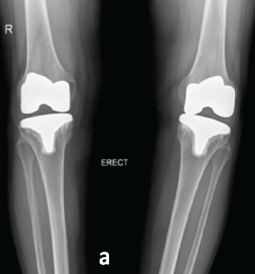

A Hybrid Surgical Approach to Late Posterolateral Instability Following Total Knee Arthroplasty: A Case Report of Posterolateral Corner Reconstruction with Component Retention

Vaibhav Bagaria , Anjali Tiwari , Shobit Deshmukh

Severe Metallosis-Induced Osteolysis and Polyethylene Liner Dissociation as a Cause of Total Knee Replacement Failure

Jipin Gopi , Abdulla Harafan , Shisham Hashim Roshan , M Aswin Ravindran , Adarsh , N R Fijad